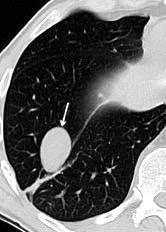

75. MASA PLEURAL MÓVIL. PLEUROLITO

Nódulo calcificado libre, móvil en la cavidad pleural. Raro. Prevalencia: 0,086% de 12.835 con 2 TC.

Más frecuente a la izquierda (75%)

Bhayana R et .Bilateral Mobile Thoracolithiasis al. Journal of Radiology Case Reports. Radiology Case. 2014.

Kinoshita F et al. Thoracolithiasis: 11 cases with a calcified intrapleural loose body. J Thorac Imaging 2010.